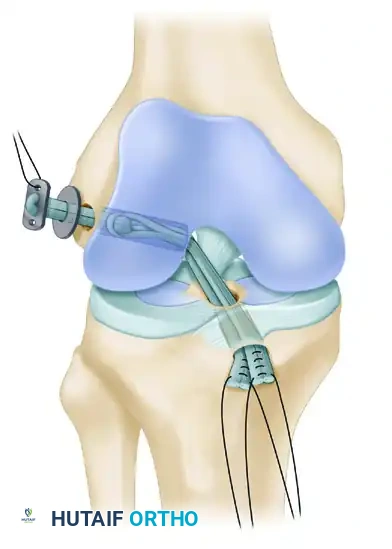

- Femoral Fixation: Pull the EndoButton and tendons up through the tibia and out the femoral hole. Because the transepiphyseal femoral hole is larger than the standard EndoButton, an EndoButton washer (Smith & Nephew, Memphis, TN) that is 3 to 4 mm larger than the femoral hole must be placed over the EndoButton. Apply distal tension to the graft, pulling the EndoButton and washer flush against the lateral femoral condyle cortex.

7. Impingement Check and Distal Fixation

- Impingement Check: Place the graft under manual tension and cycle the knee through a full range of motion. Arthroscopically evaluate for any impingement of the graft against the intercondylar notch in terminal extension. While an anterior notchplasty is rarely needed with this technique, remove a small portion of the anterior outlet if it indents the graft.

- Tibial Fixation: Position the knee in 10 degrees of flexion. Secure the quadruple hamstring graft distally by tying the No. 5 FiberWire whipstitches tightly over a tibial screw and post.

- Critical Placement: The screw and post must be placed medial to the tibial tubercle apophysis and distal to the proximal tibial physis to avoid growth disturbance.

- Augmentation: If the tendon graft extends out through the anterior tibial drill hole, augment the fixation by suturing the tendon directly to the anterior tibial periosteum using multiple No. 1 Ethibond sutures in a figure-of-eight configuration.